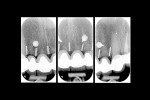

Following the insertion of the titanium bars, intraoral radiographs were taken to verify the correct positioning (Figure 11).

Radiographic evaluation of the titanium bars before the extractions and at 6 and 12 months after the extractions did not show significant changes (Figure 16).

Soft-tissue blanching was temporarily observed while the patient was biting over cotton rolls. Interdental floss could pass underneath the pontics smoothly without resistance, and it was decided to proceed with the final cementation (Figure 18). Postoperative radiographic control showed a correct interdental positioning of the bars and absence of bone resorption (Figure 19).